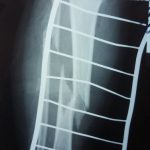

Այս ուսումնասիրությունը հիմնված է 21 հիվանդների (17 տղա, 4 աղջիկ) շարունակական խմբի բուժման արդյունքների վերլուծության վրա, որոնք ենթարկվել են տիտանե էլաստիկ մեխերով վիրահատության։ Հիվանդների տարիքը եղել է 4 տարեկանից մինչև 16 տարեկան։ 9 երեխայի մոտ կոտրվածքի պատճառ է հանդիսացել ձեռքի վրա անկումը, մնացածի մոտ կոտրվածքն առաջացել է վերջույթի ոլորման արդյունքում, վնասվածքի մեխանիզմը եղել է ուղիղ: 19 դեպքերում կոտրվածքները եղել են փակ, իսկ 2 դեպքում՝ բաց։ Ըստ վնասվածքի տեղայնացման՝ դրանք եղել են դիաֆիզար կոտրվածքներ (15 դեպք), պրոքսիմալ մետաֆիզի մակարդակի կոտրվածք (3 դեպք) և հեռավոր մետաֆիզի՝ (3 դեպք): Կոտրվածքային գծի բնույթի համաձայն՝ դիաֆիզային կոտրվածքներից հայտնաբերվել են 6 լայնակի, 4 թեք, 5 պտուտակաձև։ Մի տղայի մոտ (4 տարեկան), որի մոտ առկա էր սրունքի մ/3-ի բաց թեք կոտրվածք տեղաշարժով և մաշկի մինուս հյուսվածքներով, կատարվել է նաև վերքերի առաջնային վիրաբուժական մշակում և կարում՝ ռետինյա արտաթորիչներով։ Սակայն մի քանի շաբաթ անց սկսվել է մաշկի նեկրոզ։ Այդ իսկ կապակցությամբ կատարվել է երկրորդ վիրահատական միջամտությունը։ Կատարվել է մաշկի աուտոտրանսպլանտացիա։ Մաշկի կտորները վերցվել են առողջ ազդրի առաջային մակերեսից: (Նկ 1)